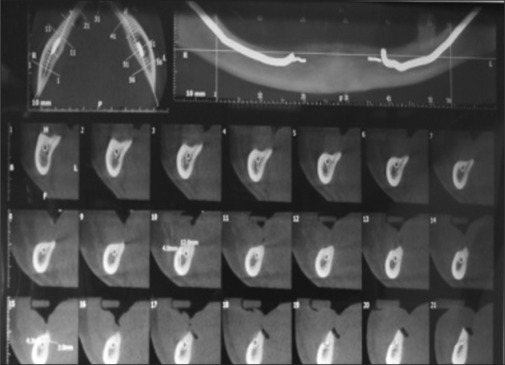

Materials and methods: The bone with respect to IAC in 60 sites from 10 patients was assessed on both sides of the atrophic mandible. Measurements were taken at 10 mm, 20 mm, and 30 mm from the mesial aspect of the retromolar pad. After assessment, 20 implants were placed bypassing IAC in five patients, and postoperatively, neurosensitivity test was performed. Descriptive analysis was used to compare the different measurements from the retromolar pad on the right and left sides. Unpaired 't' test was used. A P value less than 0.05 was considered as statistically significant.

Results: The distance of the bone relative to IAC was statistically insignificant on right and left sides. Neurosensitivity test was negative on the first postoperative day. However, after the first and third months, there was positive response on the right side in 80% subjects and 100% on the left side.

Conclusions: Dental implants were placed successfully in the atrophic mandible, bypassing the IAC. IAC is placed more lingually toward the medial border of the retromolar pad and then becomes buccally in the premolar region. Buccal bypass is safer and easier than lingual bypass due to the lingual position of IAC.